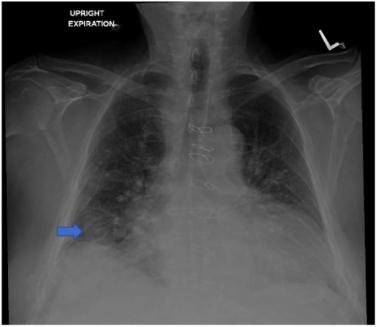

76岁男性患者,无吸烟史,有阻塞性睡眠呼吸暂停病史,接受选择性左膝全关节置换术。第二天,患者出现了非进展性连续咳嗽。胸部X线提示右肺结节状不规则阴影(图1)。胸部电脑断层扫描(CT)显示右下叶上段有一个3.2x2x4.3厘米的肿块和一个1.6厘米的颈下淋巴结(图2)。正电子发射断层扫描(PET)显示早期和延迟成像时右下叶都有活动(图3)。在身体其他部位未发现异常病灶。右下叶病变活检显示一个侵袭性,低分化,恶性黑色素瘤(图4)。患者出院后接受肺部药物治疗,两个月后接受选择性支气管镜下右下叶楔形切除术,进行淋巴结清扫和活检,并取呼吸道多处组织进行活检。最终,患者被诊断为3.7厘米的恶性黑色素瘤,边缘阴性,没有转移的迹象;因此,未发现化疗及放疗的指征。连续重复的CXR和CT扫描显示术后变化稳定,无复发迹象。到目前为止,在诊断后3年零8个月,病人继续每6个月随访一次,没有复发的记录。

图1. CXR图像。箭头:右下叶不规则肿块样阴影,无气胸、积液及实变迹象。